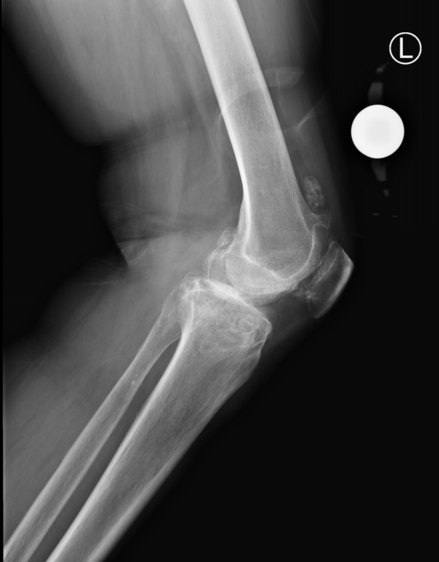

术前X线

术前规划

ROPA®人工智能骨科手术机器人手术应用